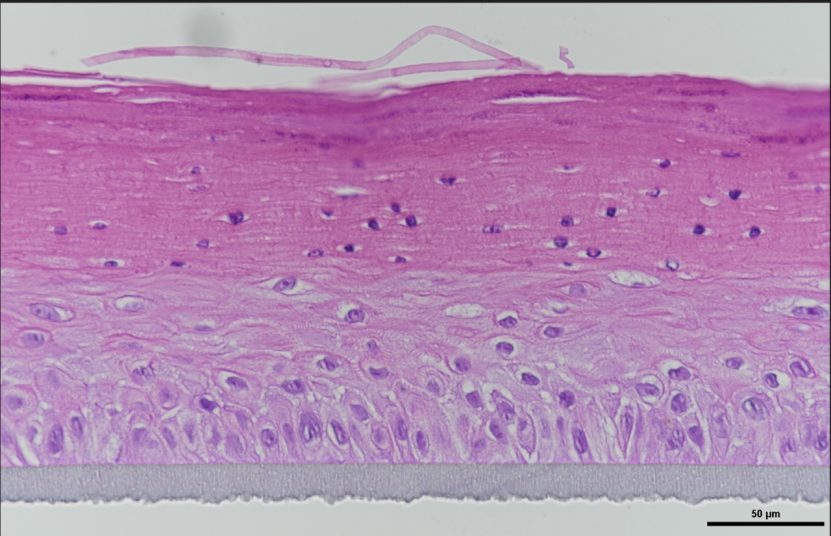

由于2D细胞模型和动物模型的种种局限,在药物临床前试验中,3D模型已成为越来越有吸引力的替代方法。皮肤病3D体外模型,通常是基于人体3D皮肤模型构建而成。人体3D皮肤模型与人类皮肤具有相似的组织结构(图1)和生物化学、生物力学特性,这些在皮肤病的发病机制中起着关键作用。皮肤病的致病原因多种多样,如接触外源性刺激、遗传因素、免疫反应等;涉及到的细胞种类也很多,如表皮层的角质形成细胞(KCs)、真皮层成纤维细胞(Fbs)、黑色素细胞以及T淋巴细胞、朗格汉斯细胞、树突状细胞(DCs)等免疫细胞。因此在进行皮肤病模型构建时,为了更加准确的阐明其发病机制,需要进行多因素、多参数的精准调控。论文通过文献检索,列举了现有皮肤病体外模型(表1)。

图1 利用生物3D打印技术构建的人体3D皮肤模型——Skinovo®-Epi